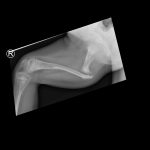

Joint stabilising procedures are usually performed at the

hip and foot. Children with CP, especially those that don’t walk, very often

develop hip dislocations. This is when the ball of the hip joint moves out of

the socket over time. A dislocated hip can become painful and it also makes it

difficult to open the legs for washing and diaper changes, and it affects

sitting. Once a hip has been dislocated for a long time, it becomes impossible

to put the hip back in joint therefore it is best to prevent the hip form

dislocating. Another commonly performed joint stabilising procedure is subtalar

fusion. With this operation, the bones of the heel of the foot are fixed

together to correct severe flatfoot.